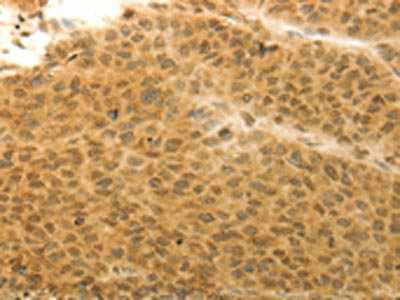

The image on the left is immunohistochemistry of paraffin-embedded Human liver cancer tissue using CSB-PA090969(HOXA4 Antibody) at dilution 1/20, on the right is treated with synthetic peptide. (Original magnification: ×200)

The image on the left is immunohistochemistry of paraffin-embedded Human colon cancer tissue using CSB-PA090969(HOXA4 Antibody) at dilution 1/20, on the right is treated with synthetic peptide. (Original magnification: ×200)